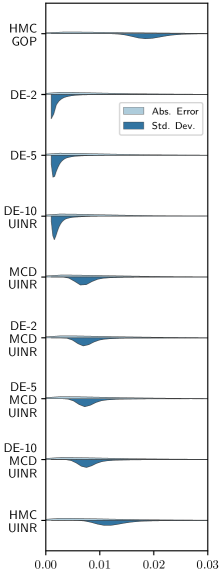

In terms of uncertainty calibration, Table 2’s results are surprising. Contrary to common BDL intuition that DEs achieve the best model calibration (Ovadia et al., 2019), we found MCD to be more effective for INR UQ calibration. Specifically, MCD UINRs and DEs of MCD UINRs achieved significantly better model calibration than DEs of INRs without uncertainty. For example, introducing MCD to a DE-10 UINR reduced ECE from 0.144 to 0.045 (60-views) and from 0.162 to 0.053 (120-views). Although increasing ensemble sizes generally improved model calibration, the performance boost was not as significant as that of using MCD. We do not currently have a full understanding of why DEs perform poorly relative to MCD for UINRs, in contrast to standard BDL applications. However, in Section F.6, we hypothesize that this may be due to the model capacity of an individual ensemble member, which is dictated through the RFF encoding frequency .

The benefits of MCD for INR calibration are further illustrated by the violin plots of Figure 3a, comparing the pixel-wise absolute error versus predicted standard deviation distributions across GOP and UINR models. For non-MCD DEs, the standard deviation distribution skews towards smaller values than the absolute error distribution, indicating that the model is overconfident. The opposite is true for HMC GOP, which is underconfident. Meanwhile, HMC and MCD UINRs predicted standard deviation distributions most closely resembling those of the absolute error, indicating decent calibration.